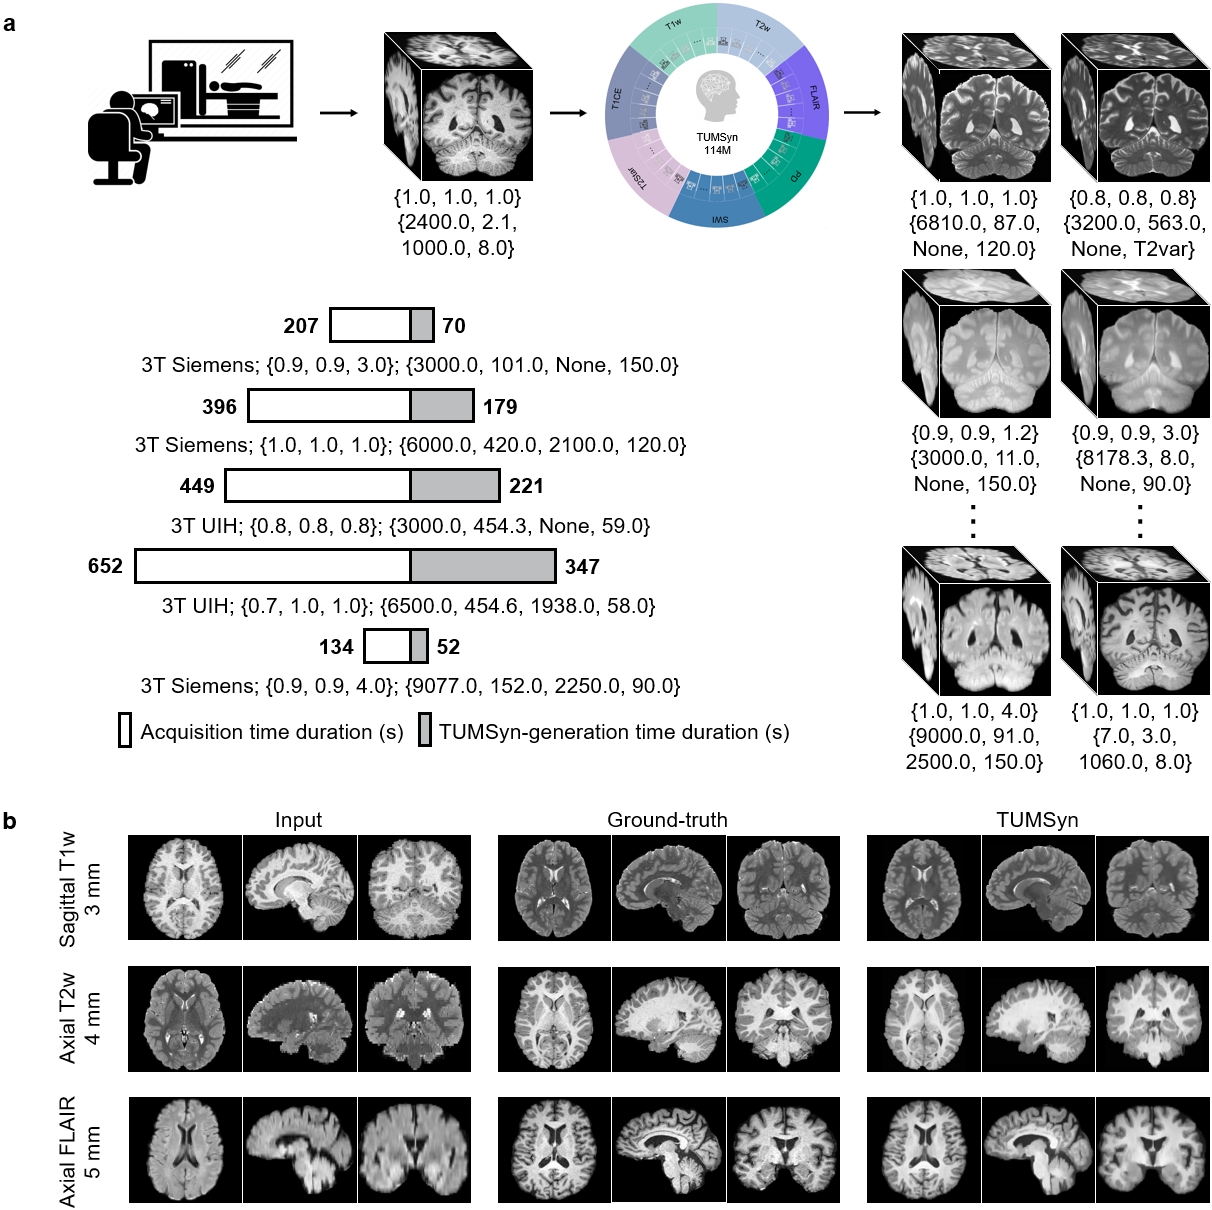

The abovementioned merits endow TUMSyn with great potential to be integrated into MRI-assisted clinical workflows (Fig.2 a). Specifically, once the MRI scanner has acquired any routine MR sequence from a subject, TUMSyn can generate complementary MRI sequences with specified imaging parameters in real time, which can potentially greatly benefit the follow-up diagnosis. Besides, compared to real MR scanning, TUMSyn reduces imaging duration by 2- to 4-fold while maintaining clinical equivalence with no additional cost. To validate TUMSyn’s adaptability to heterogeneous real-world scenarios, we showcased the performance of TUMSyn in synthesizing customized images from various inputs (Fig.2 b). In all cases, TUMSyn generates promising images via the guidance of text prompts, underscoring its proficiency in accurate image generation with preserved image details across arbitrary upsampling and cross-modality translation tasks. It is worth noting that the integration of generative models in MR imaging opens up the opportunity for synthesis-empowered MR scanning and MRI-assisted diagnosis.

TUMSyn in improving synthesis accuracy and versatility

To study TUMSyn’s synthesis accuracy and ability for diverse tasks using a unified model, we performed a systematic evaluation of TUMSyn on a broad spectrum of synthesis tasks using nine internal datasets. First, we compared TUMSyn with three competing models, including SC-GAN [27], One-hot model, and BiomedCLIP [20] model. SC-GAN is a self-attention-based conditional GAN for MR neuroimaging synthesis, and it is a task-specific network trained for independent tasks. The One-hot model and BiomedCLIP model, sharing the identical image synthesis model architecture as ours but utilizing one-hot encoding and BiomedCLIP for text embedding, respectively, are employed to evaluate the effectiveness of our pre-trained text encoder on brain MRI synthesis. The comparison includes eight synthesis tasks for commonly used MRI modalities on internal test sets (Fig.3). The results exhibit that TUMSyn achieves the highest performance for all the tasks. Specifically, TUMSyn significantly outperforms task-specific SC-GAN with both improved PSNR (up to 2.86 dB) and SSIM (up to 0.044). This finding suggests that training on varied data and tasks enables the model to learn generic feature representations, thereby enhancing its overall synthesis ability for different scenarios. Besides, compared to the One-hot model, leveraging text prompts can lead to greatly improved synthesis performance, probably because text prompts can precisely instruct imaging parameters of target images.Moreover, it is shown that, although BiomedCLIP is trained on substantially larger biomedical datasets, our pre-trained text encoder empowers the synthesis model to achieve higher PSNR (up to 1.12 dB) and SSIM (up to 0.010) across eight tasks. This suggests that allowing the text encoder to learn task-related information, namely MR imaging parameters, is critical in enhancing MR image synthesis performance, especially for the downstream tasks that requiring precise prompt features as guidance.

Visual evaluation is presented in Fig. 4. Besides the aforementioned comparison methods, a general method dedicated to synthesizing T1w images, SynthSR [28], is further enrolled into comparison. We observe that, since the PD images in the IXI dataset are acquired from two centers using different imaging protocols, the output images of TUMSyn are much more accurate in anatomical details especially compared to SC-GAN, One-hot model, and SynthSR (Fig. 4 a). These observations once again underscores the importance of utilizing imaging parameters and demographic information as textual prompts to guide accurate image synthesis.